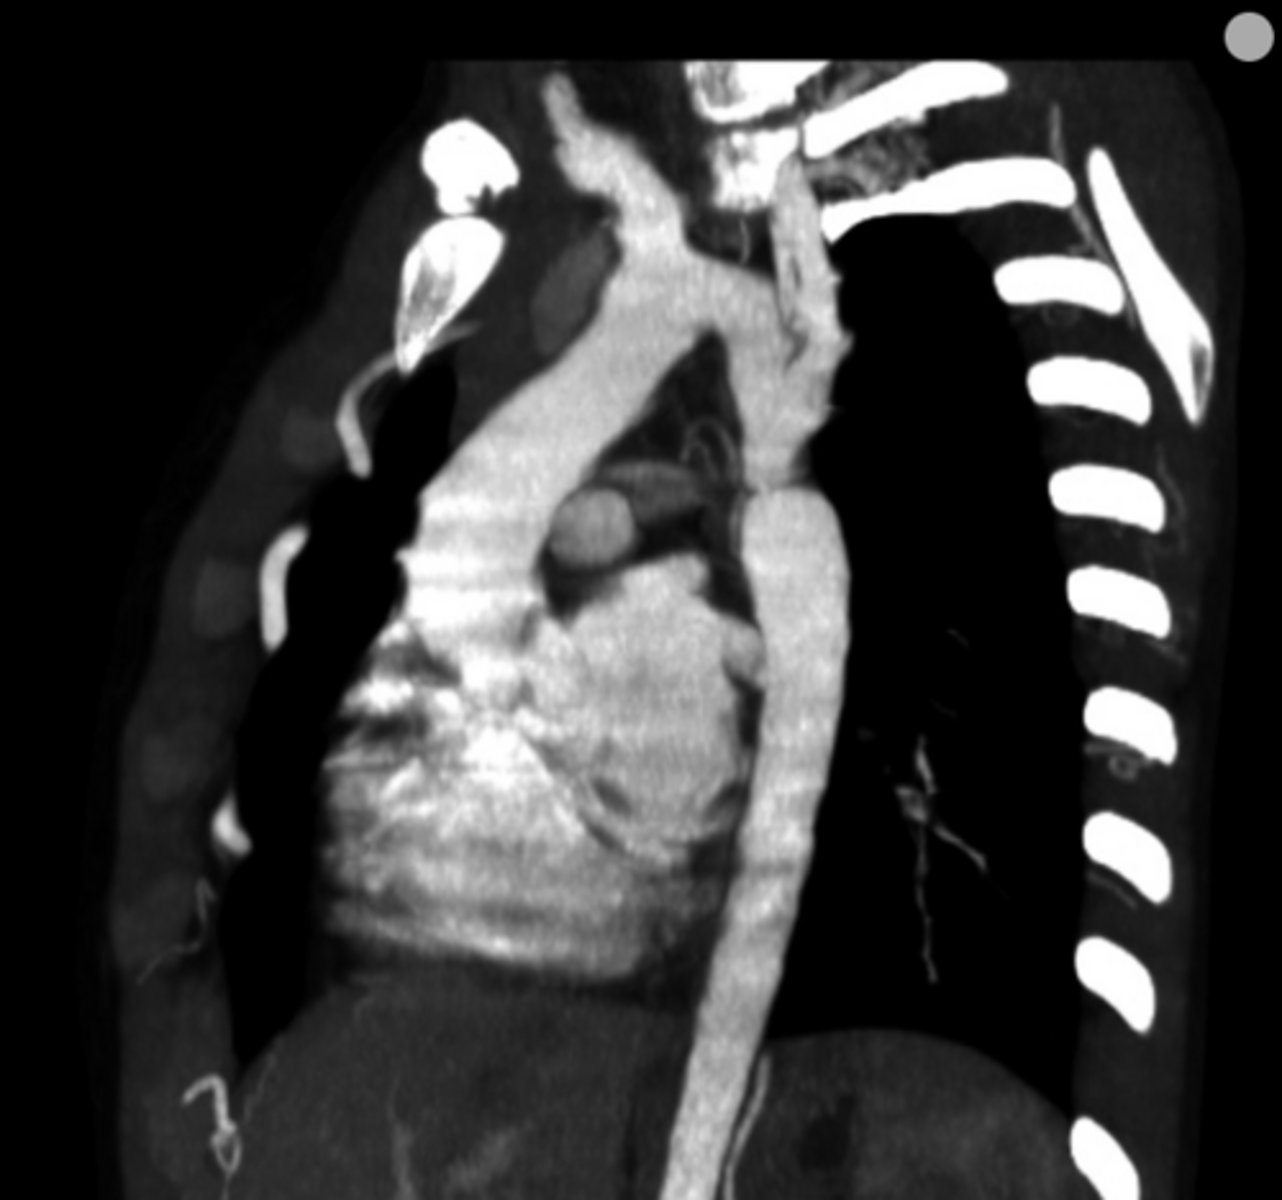

What is coarctation of the aorta?

Congenital narrowing of the aorta.

<p>Congenital narrowing of the aorta.</p>

What are the key features of infantile coarctation of the aorta?

Symptomatic in early childhood, tubular hypoplasia of the aortic arch, occurs proximal to a PDA.

<p>Symptomatic in early childhood, tubular hypoplasia of the aortic arch, occurs proximal to a PDA.</p>

What are the key features of adult coarctation of the aorta?

Narrowing opposite a closed ductus arteriosus, distal to the great vessels from the aortic arch.

<p>Narrowing opposite a closed ductus arteriosus, distal to the great vessels from the aortic arch.</p>

What is the chest radiograph finding in coarctation of the aorta?

Figure 3 sign.

<p>Figure 3 sign.</p>